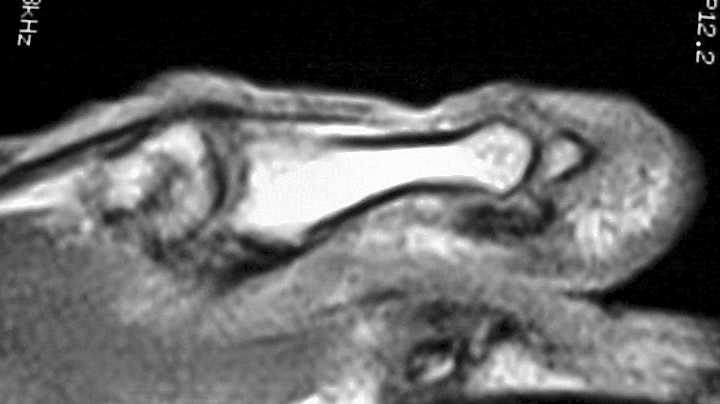

MRI demonstrated ill defined soft tissue replacement of the majority of the distal phalanx:

Click for larger image